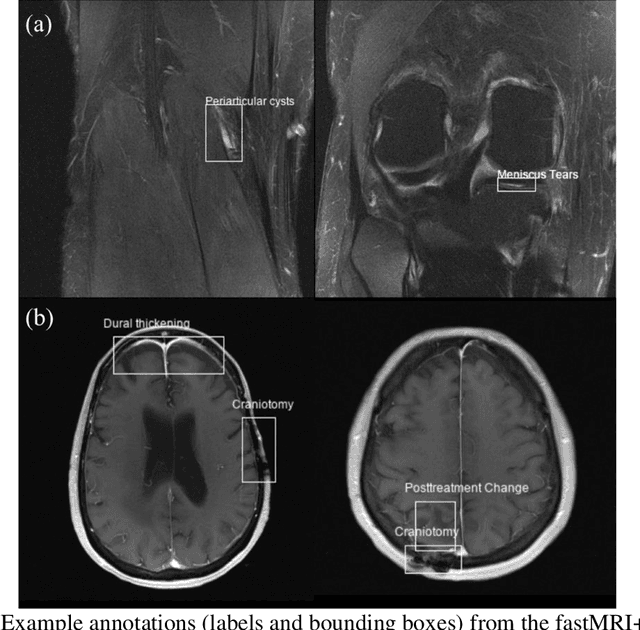

Abstract:Improving speed and image quality of Magnetic Resonance Imaging (MRI) via novel reconstruction approaches remains one of the highest impact applications for deep learning in medical imaging. The fastMRI dataset, unique in that it contains large volumes of raw MRI data, has enabled significant advances in accelerating MRI using deep learning-based reconstruction methods. While the impact of the fastMRI dataset on the field of medical imaging is unquestioned, the dataset currently lacks clinical expert pathology annotations, critical to addressing clinically relevant reconstruction frameworks and exploring important questions regarding rendering of specific pathology using such novel approaches. This work introduces fastMRI+, which consists of 16154 subspecialist expert bounding box annotations and 13 study-level labels for 22 different pathology categories on the fastMRI knee dataset, and 7570 subspecialist expert bounding box annotations and 643 study-level labels for 30 different pathology categories for the fastMRI brain dataset. The fastMRI+ dataset is open access and aims to support further research and advancement of medical imaging in MRI reconstruction and beyond.